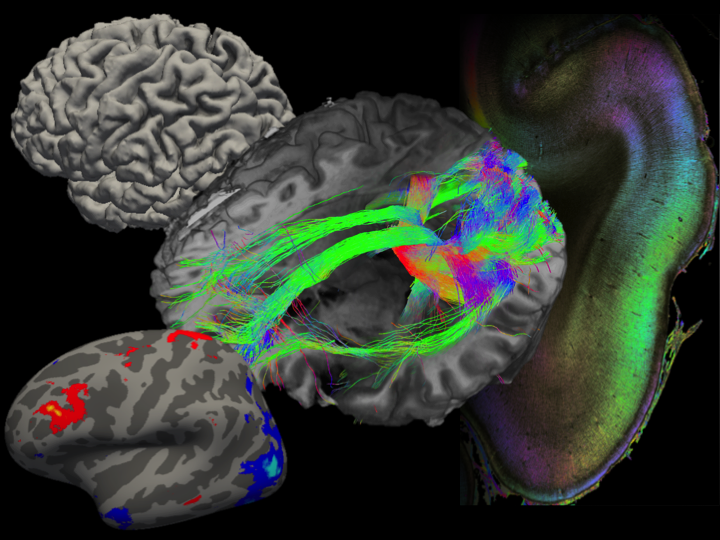

The institute division of Structural and Functional Organization of the Brain (INM-1) is developing a three-dimensional digital atlas of the human brain. For this purpose, areas of the cerebral cortex, subcortical core areas, as well as fiber webs in post-mortem brains are mapped. In order to do justice to the enormous complexity of the human brain, our approach consists in the integration of cyto- and receptorarchitectural, genetic and functional as well as PLI-based maps into a multi-modal atlas of the brain. For this purpose, we develop methods for image analysis and 3D reconstruction, artificial neural networks and big-data analysis with supercomputing.

The „BigBrain“, an ultra-high resolution brain model, and the Julich-Brain, a cytoarchitectural atlas reflecting variations in brain structure, are results of our research.We make our brain maps available to the scientific community. They are part of the HBP Human Brain Atlas and can be merged with neuroimaging data via the Anatomy Toolbox.